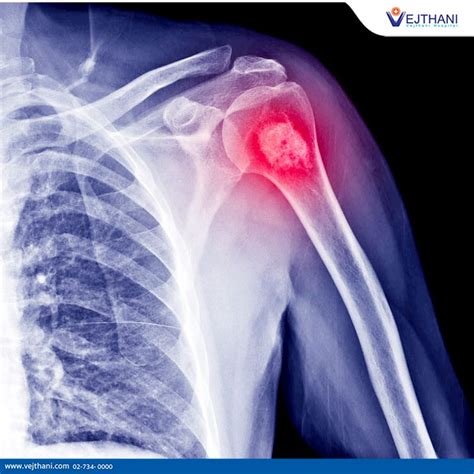

Hey guys, let’s dive into osteosarcoma , a topic that might sound a bit intimidating, but understanding it is super important, especially when we’re talking about cancer. So, what exactly is osteosarcoma? Essentially, it’s a type of bone cancer that typically starts in the long bones of the arms or legs, but it can also occur in other bones, including the pelvis, and even the jaw. What makes osteosarcoma particularly noteworthy is that it’s the most common type of bone cancer found in children and young adults. This is a crucial piece of information because it highlights the need for early detection and effective treatment strategies tailored for this demographic. The American Cancer Society provides a wealth of information on osteosarcoma, and it’s a great resource for anyone looking to get a deeper understanding of this disease. They break down complex medical information into digestible pieces, making it accessible to patients, their families, and even healthcare professionals who want to stay updated. When we talk about osteosarcoma, we’re referring to a cancer that originates from the bone-forming cells, known as osteoblasts. These cells normally help create new bone tissue, but in osteosarcoma, they grow abnormally and uncontrollably, forming a malignant tumor. This abnormal growth can then invade surrounding tissues, and in some cases, it can spread, or metastasize, to other parts of the body, most commonly to the lungs. The aggressive nature of osteosarcoma is one of the primary challenges in its treatment. Early diagnosis is absolutely key, as it significantly improves the chances of successful treatment and a better prognosis. The journey through understanding and battling osteosarcoma can be daunting, but knowledge is power, and the American Cancer Society aims to empower individuals with that knowledge. They cover everything from the signs and symptoms to the diagnostic process, various treatment options, and the ongoing research efforts to find better ways to combat this disease. It’s vital for us to be aware of the potential signs, even if they seem minor at first. Often, the first symptom noticed is pain in the affected bone, which might be mistaken for a sports injury or growing pains in younger individuals. This is why it’s so important not to dismiss persistent pain. The American Cancer Society’s role in disseminating information about osteosarcoma cannot be overstated. They act as a beacon of hope and a reliable source of information in the often confusing landscape of cancer. Their commitment to educating the public and supporting research means that more people are aware of osteosarcoma, leading to earlier diagnoses and ultimately, better outcomes for patients. So, whether you’re a patient, a caregiver, a student, or just someone interested in health, delving into what the American Cancer Society has to say about osteosarcoma is a really worthwhile endeavor. They shed light on the complexities of this bone cancer, offering clarity and guidance to navigate this challenging disease. It’s about fostering a community of informed individuals who can advocate for themselves and their loved ones, and support the ongoing fight against osteosarcoma.

Alright, let’s talk about the signs and symptoms of osteosarcoma , because knowing what to look out for can make a world of difference, especially for our younger folks and their families. It’s super common for parents and kids to dismiss early signs, thinking it’s just a bump or bruise from playing sports, but persistent symptoms really shouldn’t be ignored. The American Cancer Society really emphasizes how crucial early recognition is. So, what are the most common red flags? The pain in the affected bone is usually the first symptom people notice. This pain might start mild and come and go, but it tends to get worse over time, especially at night or during physical activity. It’s often described as a deep ache or soreness. Think of it like this: if your child complains of leg pain that doesn’t get better with rest, or wakes them up at night, it’s definitely worth getting checked out. Another key symptom is a swelling or lump in the affected area. As the tumor grows, it can cause a noticeable mass or swelling, particularly around the knee or thigh, which are common sites for osteosarcoma. This lump might not always be painful initially, but it can make movement difficult and cause a limp if it’s in a leg bone. So, if you feel a lump that wasn’t there before, or notice swelling that persists, that’s another sign to take seriously. Some individuals might experience limited range of motion in the affected limb. If the tumor is near a joint, it can restrict movement, making it harder to bend or straighten the limb. This can affect daily activities like walking, running, or even picking things up. A fracture in the affected bone can also be a symptom, though it’s less common as an initial sign. Because osteosarcoma weakens the bone, it can sometimes break with little or no trauma. This is called a pathological fracture, and it can sometimes be the first indication that something is wrong. If a bone breaks unexpectedly, especially in someone with no history of injury, doctors will investigate further. It’s also important to be aware of systemic symptoms , although these are less specific to osteosarcoma itself. Some people might experience unexplained weight loss, fatigue, or fever. These symptoms are more general and can be caused by many other conditions, but if they occur alongside bone pain or swelling, it’s an important piece of the puzzle for doctors to consider. The American Cancer Society provides detailed guides on these symptoms, aiming to equip parents and young people with the knowledge to seek medical attention promptly. They stress that not everyone with these symptoms will have osteosarcoma, but it’s always better to be safe than sorry. Early diagnosis is truly a game-changer for osteosarcoma treatment. When caught early, treatment can be more effective, and the chances of a full recovery are significantly higher. So, guys, pay attention to your bodies, and if you notice any persistent pain, swelling, or changes in mobility, especially in your arms or legs, don’t hesitate to consult a doctor. It’s always better to have it checked out and find out it’s nothing serious than to delay seeking help for something that could be.

So, you’ve noticed some concerning symptoms, and you’re wondering, “What happens next?” This is where the diagnosis and staging of osteosarcoma come into play, and it’s a critical part of the whole process, as highlighted by the American Cancer Society. Getting a clear diagnosis is the first hurdle, and then understanding the stage helps doctors figure out the best treatment plan. The diagnostic journey usually begins with a thorough physical examination and a detailed discussion about your medical history and symptoms. After that, imaging tests are key. X-rays are often the very first step. They can show abnormal changes in the bone, like a tumor or a fracture. If an X-ray suggests a possible bone tumor, then more advanced imaging techniques are usually ordered. CT scans (Computed Tomography) are excellent for providing detailed cross-sectional images of the bone and surrounding soft tissues. They can help doctors see the size of the tumor and if it has invaded nearby structures. MRI scans (Magnetic Resonance Imaging) are also very important. They give even more detailed images, especially of soft tissues, and are particularly good at showing how far the tumor has spread into the bone marrow or into nearby muscles and blood vessels. Bone scans might also be used. In this test, a small amount of radioactive material is injected into a vein, and it accumulates in areas of increased bone activity, which can highlight the tumor and also show if cancer has spread to other bones. To confirm that it is indeed osteosarcoma and not some other condition, a biopsy is essential. This is where a small sample of the suspected tumor tissue is removed, either through a needle biopsy or a surgical biopsy, and examined under a microscope by a pathologist. The pathologist looks for the characteristic malignant bone cells that define osteosarcoma. This step is absolutely crucial because it confirms the diagnosis and helps determine the specific type and grade of the tumor, which impacts treatment decisions. Once osteosarcoma is confirmed, the next step is staging . Staging is the process of determining the extent of the cancer – how large the primary tumor is, whether it has spread to lymph nodes, and if it has metastasized to distant parts of the body, most commonly the lungs. The American Cancer Society explains that staging helps doctors predict the prognosis and plan the most effective treatment. The most common staging system used for osteosarcoma is the TNM system (Tumor, Node, Metastasis), but for bone cancers, surgeons often use a system that categorizes tumors based on whether they are contained within the bone (localized) or have spread outside the bone (regional or distant). The grade of the tumor is also a critical factor. Tumor grade refers to how abnormal the cancer cells look under a microscope and how quickly they are likely to grow and spread. High-grade tumors are more aggressive and have a poorer prognosis than low-grade tumors. The stage and grade together give doctors a comprehensive picture of the cancer’s status. For example, stage I cancers are typically low-grade and localized, while stage IV cancers have likely metastasized. The American Cancer Society provides detailed information on these stages, helping patients and their families understand what each means for their treatment journey. This detailed diagnostic and staging process is fundamental for tailoring a personalized treatment approach, which is vital for maximizing the chances of successful outcomes in the fight against osteosarcoma.